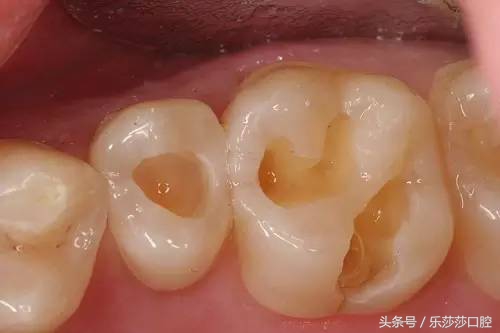

早期的大牙有蛀牙是没有明显的龋洞,大多在咬合面有黑色的勾线,很多患者都以为那是色素沉着,洗牙时总是要求尽力把那洗去,殊不知那其实已经是龋坏。其发展主要有三个阶段:

1、蛀牙基本形成,沟壑内附着细菌,牙齿表面黑线形成。

2、蛀牙侵蚀到牙本质内部,吃东西遇到冷热酸甜会感到 不适,也由原来的黑线发展成较大的蛀洞。

前牙咬合面(就是吃东西时咀嚼的那面)较窄,是一条细长的现状,咬合面比较平整光滑,而大牙(后牙)咬合面面积较大,像个磨盘一样,起到增大咀嚼面积,增加摩擦力的作用,但是,上面有沟壑裂纹,坑坑洼洼,就像地砖间的缝隙死角,残渣,脏东西很容易残留在缝隙里堆积,形成卫生死角。